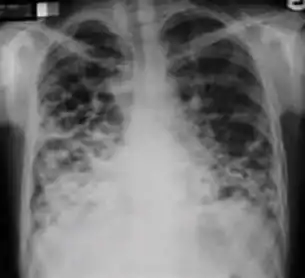

1. Infiltrate or consolidation - Opacification of airspaces within the lung parenchyma. Consolidation or infiltrate can be dense or patchy and might have irregular, ill-defined, or hazy borders.

Dense homogenous opacity in right, middle and lower lobe of primary pulmonary TB.

Chest x-ray showing patchy opacification on the upper right and mid-zone lung with fibrotic shadows, as well as bilateral hilar lymphadenopathy.